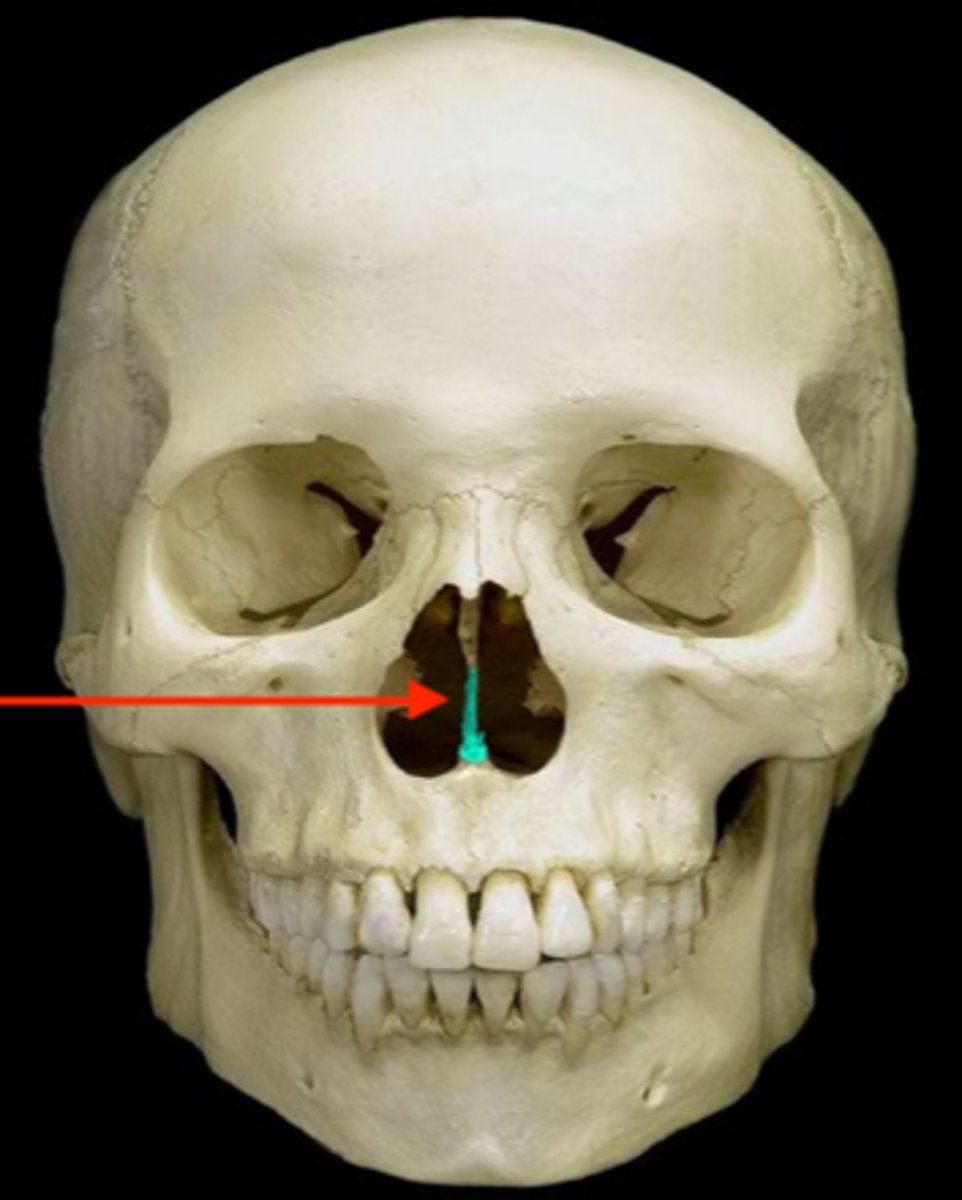

Perpendicular Plate of Ethmoid Bone

Cristi Galli

Cribriform plate of ethmoid

Superior and Middle Nasal Conch

Vomer

Inferior Nasal Concha